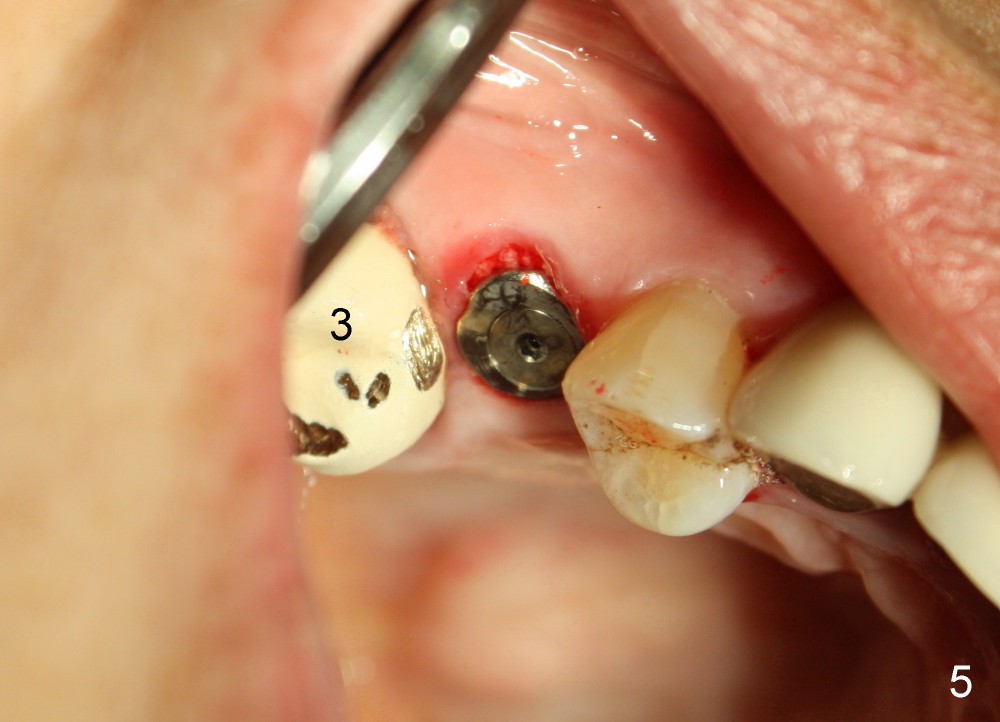

Immediate provisional is aborted due to low torque value and patient's in-cooperation (fear). A healing cuff (4.5 mm in diameter) is placed to close the buccal gap (Fig.5). The joined crowns are separated. The crown for #3 is recemented. Finally perio dressing is placed around the implant. The healing cuff is removed 6 days postop because of pressure. The patient returns for restoration 9 months postop. The gingival tissue is healthy around the implant (Fig.6). The bone density around the implant increases (Fig.7 *, compare to Fig.4).